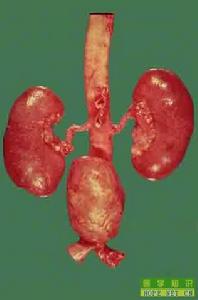

動脈粥樣硬化 AS是一種與血脂異常及血管壁成分改變有關的動脈疾病,主要累及大動脈(彈力型—主動脈及其一級分支)、中動脈(彈力肌型—冠狀動脈、腦動脈等),病變特徵是血中脂質在動脈內膜沉積、平滑肌 細胞(smooth muscle cell, SMC)和結締組織增生,引起內膜灶性纖維性增厚及粥樣斑塊形成,使動脈壁變硬,管腔狹窄。

動脈粥樣硬化 它是一種以中等和大動脈斑片狀內膜下增厚(動脈粥樣化)為特徵的病變,可以減少或阻斷血流。斑塊部位的動脈壁增厚、變硬,斑塊內部組織壞死後與沉積的脂質結合,形成粥樣物質,稱為粥樣硬化。

其特點是受累動脈的內膜有類脂質的沉著,複合糖類的積聚,繼而纖維組織增生和鈣沉著,並有動脈中層的病變。本病主要累及大型及中型的肌彈力型動脈,以主動脈、冠狀動脈及腦動脈為多見,常導致管腔閉塞或管壁破裂出血等嚴重後果。動脈粥樣硬化多見於40歲以上的男性和 絕經期後的女性。本病常伴有 高血壓、高膽固醇血症或 糖尿病等。腦力勞動者較多見,對人民健康危害甚大,為老年人主要病死原因之一。

粥樣硬化斑塊通常是散在的,可以在主動脈至直徑3mm的動脈內膜發生,最常見於冠狀動脈,是 冠心病的主要發病原因。

動脈造影:可顯示四肢動脈、腎動脈與冠狀動脈由於粥樣硬化所造成的管腔狹窄、病變部位及範圍。